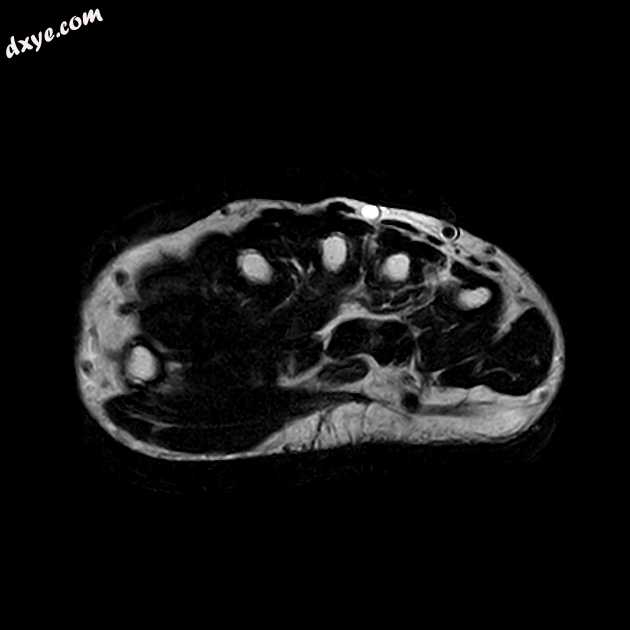

Axial T2

掌侧尺侧囊液信号肿胀,T1低信号,T2高信号,T2高信号PD.FS滑膜增厚,包绕屈指肌腱,主要位于前臂远端水平,经腕管向远端延伸至掌骨干水平。局灶性滑膜增厚可见深至趾深屈肌内侧部,在序列上有中间信号。正中神经肿胀,信号改变,提示腕管综合征。

右手腕MRI表现为掌尺滑囊炎伴深至指深屈肌内侧部的局灶性结节性滑膜炎,其次为腕管综合征。